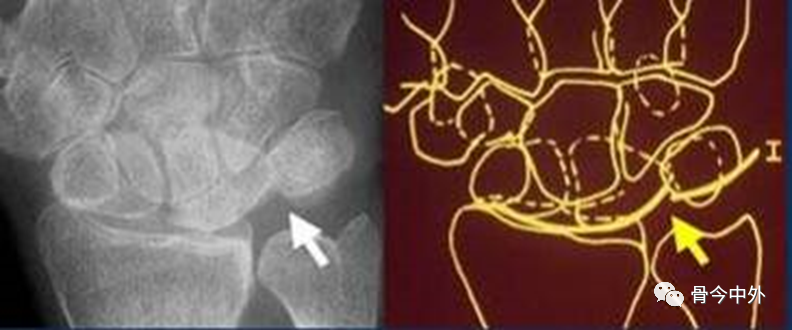

图18

弧线Ⅱ 中断于舟月关节和月骨-三角骨关节(上图)。弧线Ⅰ虽有缺口但仍呈光滑弧线,可认为是完整的。